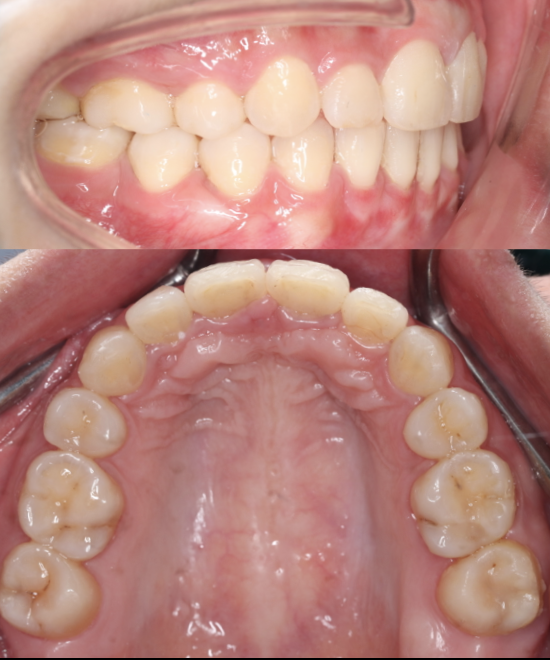

Smile Makeover

This case involved an occlusal issue with Class III incisor malocclusion. The patient was treated with a comprehensive smile makeover, including crowns on #11 and #21, e-max veneers on adjacent teeth, and Beyond Plasma Whitening on the lower arch. The result is a beautifully balanced, brighter smile — both functional and aesthetic, proudly completed at Moral Dental Clinic.